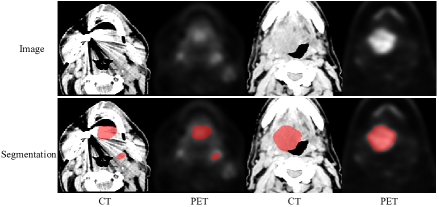

Refer to caption

Figure 1: Visual examples of PET and CT image and the corresponding ground truth.